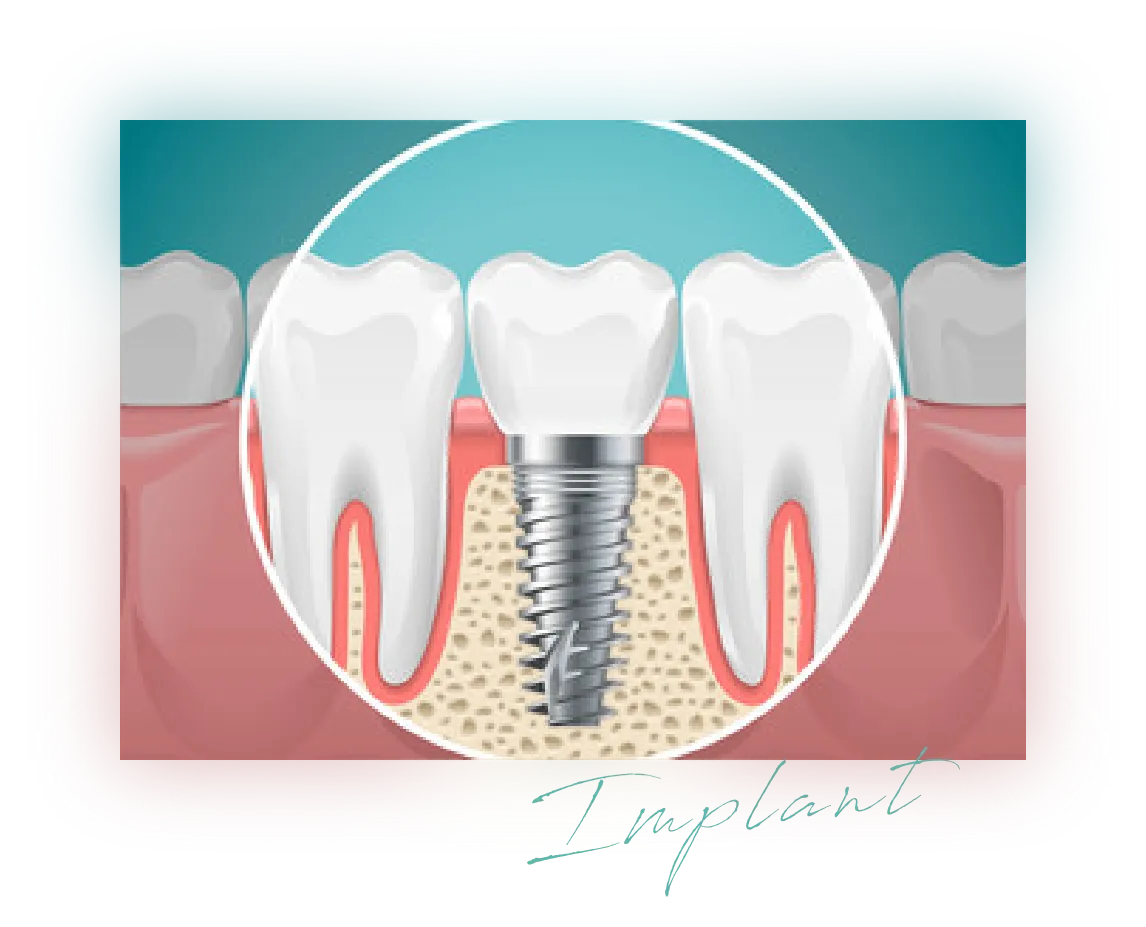

インプラント治療は、チタン製の人工根を歯茎に埋め込み、そこに人工歯を装着する外科手術です。

オールセラミックを使えば自然な見た目と強い噛む力が可能となり、他の歯を守りつつ、まるで本来の歯のような仕上がりになります。